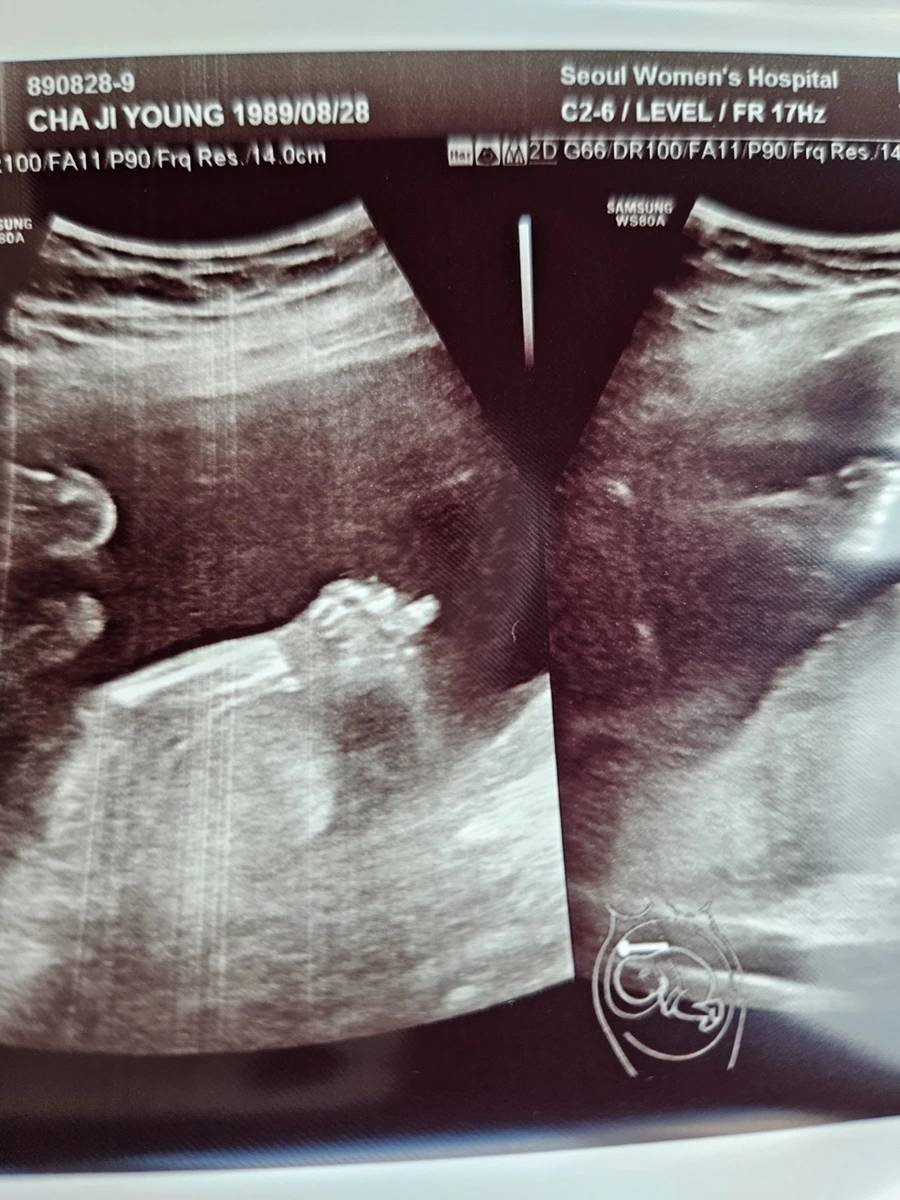

이전에 짧게 짧게 머리둘레, 배 등 간단히 보던 초음파와 다르게 영상 속에서 아기가 활발하게 움직이는 모습과 얼굴까지 포착되니 남편과 나는 정말 신기했다. 뱃속에서 아기가 다섯개의 손가락과 다섯개의 발가락 뿐만 아니라 포즈를 취하면서 놀고 있는 모습을 본다는 것이 정말 생경한 경험이었다.

남편도 이 날 초음파를 보면서 개념적으로만 알던 아기의 존재를 움직이고 살아있는 존재로 만나니 정말 아빠가 된 듯한 느낌이었다고 말했다. 모든 것이 정말 정말 신기했다. ’반짝아, 너 정말 거기에 있구나!ㅎㅎㅎ 모든 것이 처음인 엄마와 아빠는 너가 양 손을 들어 올려 얼굴을 가리고 손을 흔들 흔들 하고 있는 모습에 반했어. 너무 신기한거 있지? 손가락을 빨기도 했다가, 마지막에는 peace를 하며 손가락을 오므린 너의 모습을 보면서 감동의 감동을 했다!’